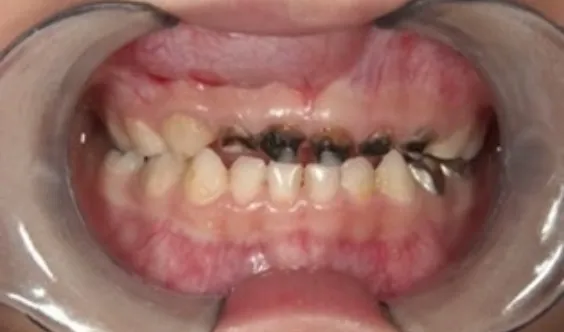

• 上の前歯が黒く虫歯になっている歯列

哺乳瓶で糖分のある

ものを飲ませていたお口